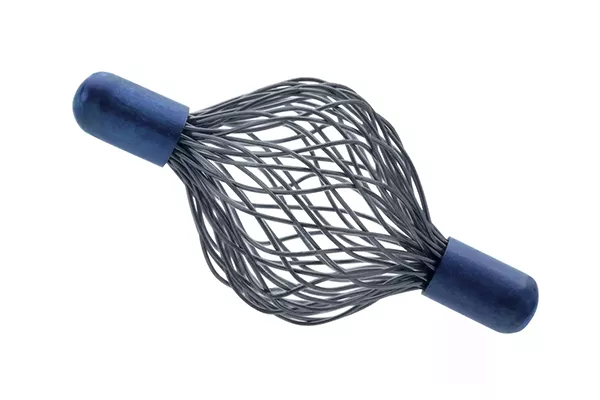

SecurMark™ Biopsy Site Markers

Designed to minimise movement,2 this marker is highly visible in ultrasound upon deployment and still highly visible at 6 weeks post-biopsy, crucial in case of future breast interventions.3 The marker consists of two pieces, a permanent marker and a bioabsorbable suture-like netting.